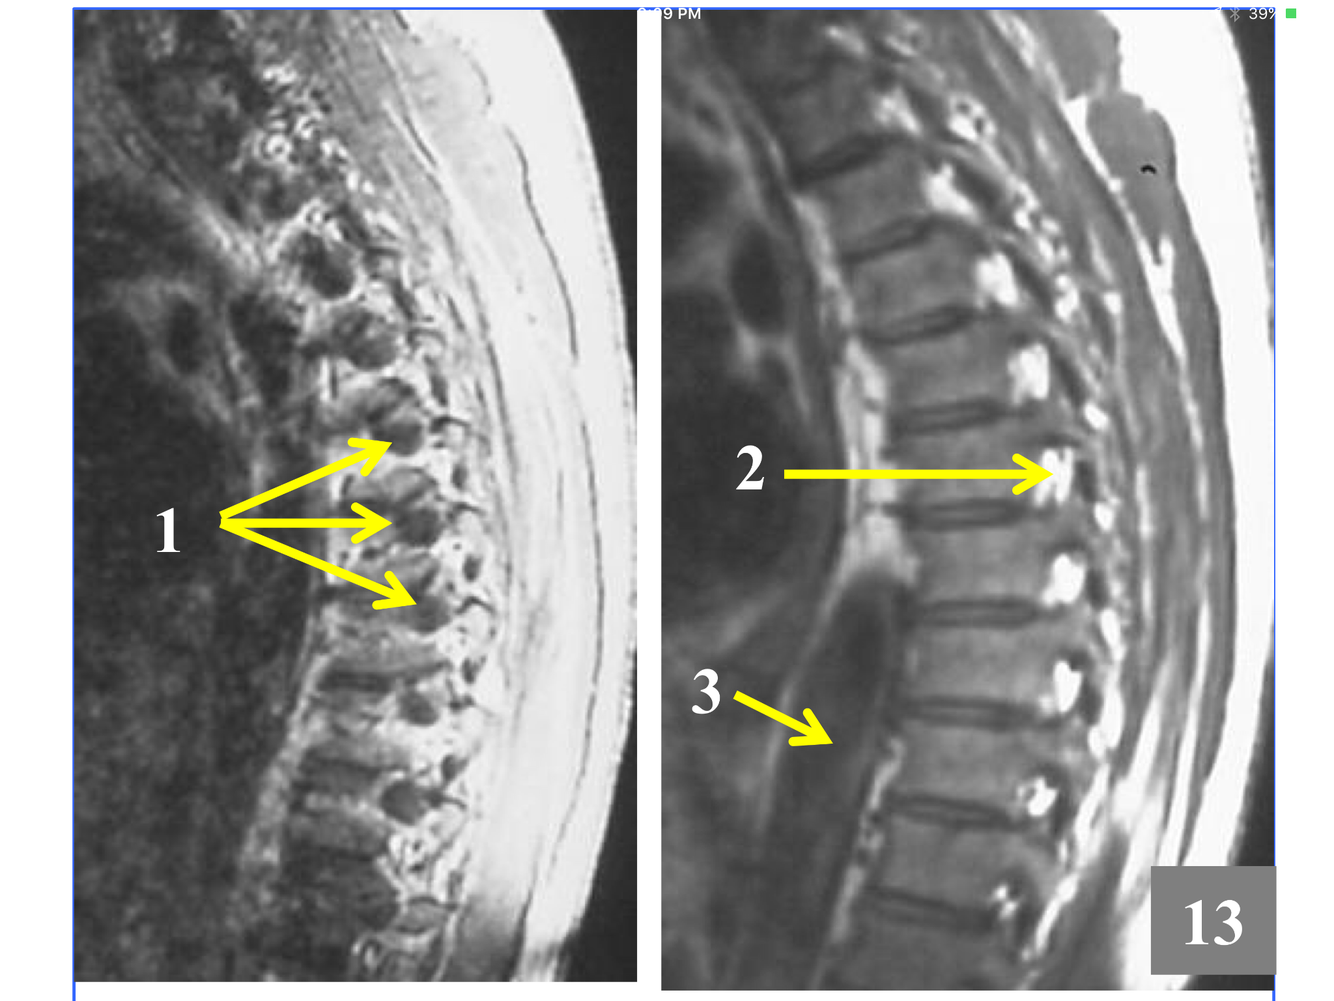

* The stack of inferior and superior articulating processes, and the zygapophyseal joints they form

*Comprised of the inferior and superior articulating processes, and the zygapophyseal joints they form

*Although the transverse process is not seen, the tubercle articulates with the transverse costal facet on it.

*Immediately above the conus, which is at L1-L2